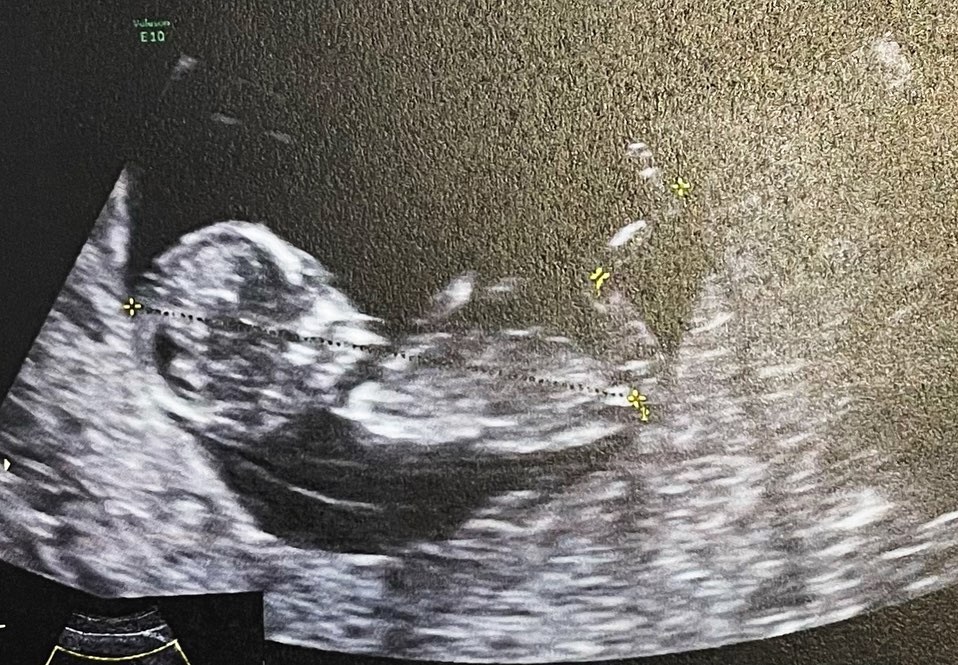

โดยในภาพนั้น เป็นภาพตนเองและสามี กับรูปอัลตราซาวน์ลูกน้อย ในมือของว่าที่คุณแม่ ทั้งนี้น้ำชายังระบุข้อความว่า "Our+1" ท่ามกลางความยินดีของเหล่าคนในวงการบันเทิง และแฟนคลับเป็นจำนวนมาก